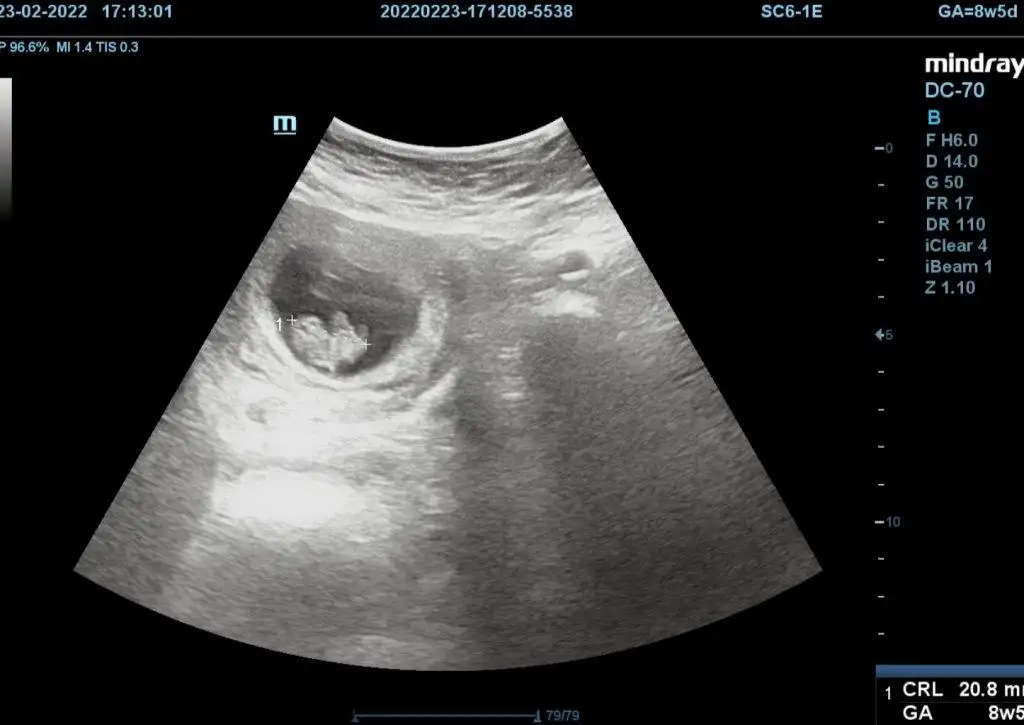

5 ve 14. haftaya kadar olan ultrasyon fotolarınızı paylaşın. Vajinadan mı yoksa karından mı çekildiğini ve kaç haftalık olduğunu da mutlaka belirtin.

Not: Tahmin yaptığım anneler cinsiyet öğrendikten sonra lütfen bana geri dönüş yapın![]()